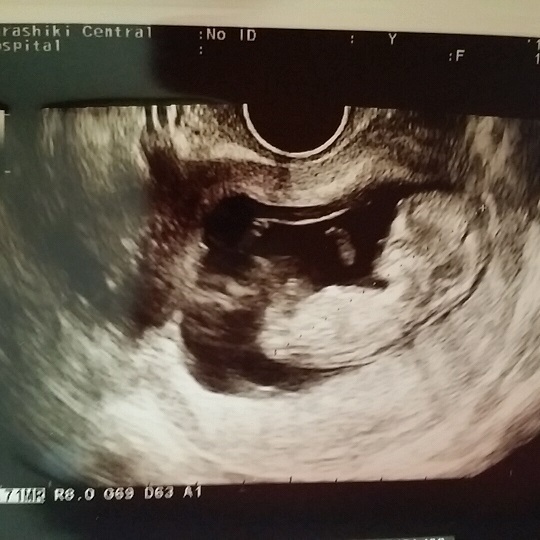

11週0日(11w0d・性別不明)|kiki34 さん(28歳)

エコー写真撮影時のエピソード:

両親や姉妹に報告するときにエコーの写真を見せました。とても喜んでもらえました。 毎回のエコー写真はアルバムにしてコメントをつけて保存するようにしています。

だんだん大きくなっているのが目に見えてわかりコメントを書くことによってその時の気持ちがわかるようになるので見返してて楽しいです。将来は産まれてきた我が子にあげる予定です!